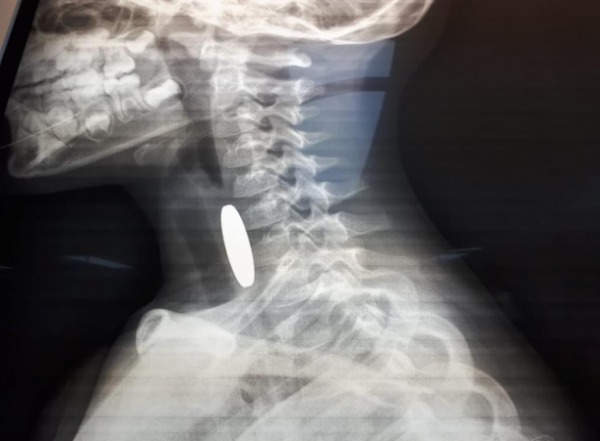

أنقذت مرتبات دورية نجدة تابعة لشرطة مادبا أثناء الوظيفة الرسمية حياة طفل يبلغ من العمر ثلاثة أعوام ونصف، بعد أن تعرض لحادثة اختناق إثر ابتلاع عملة معدنية في منطقة لواء ذيبان. وفي التفاصيل، قال والد الطفل محمد الجديعات لإذاعة الأمن العام، إنه وبعد أن لاحظ أن طفله يجد صعوبة بالتنفس قام بشكل فوري بإسعافه باتجاه مستشفى الأميرة سلمى الحكومي، حيث صادف وجود دورية نجدة على مقربة من منزله وعلى الفور استنجد بهم، ليقوم أفراد الدورية بتقديم الإسعافات الأولية اللازمة باحترافية لمثل هذه الحالات بعد أن ابلغهم أنه قد ابتلع قطعه معدنية . من جانبه قال الوكيل علاء السلايطة، أحد أفراد الدورية: “أثناء وجودنا في المنطقة استنجد بنا والد الطفل وهو يحمل ابنه، فقمنا مباشرة بتقديم الإسعافات الأولية المخصصة للأطفال دون سن الخامسة، وفقاً للتدريبات والدورات التي نتلقاها من مديرية الأمن العام للتعامل مع مثل هذه الحالات حتى بدأت حالته الصحية بالاستقرار واستكمال عملية إسعافه باتجاه المستشفى بواسطة المحطة الأمنية بعد أن تم التنسيق مع غرفة العمليات والسيطرة.